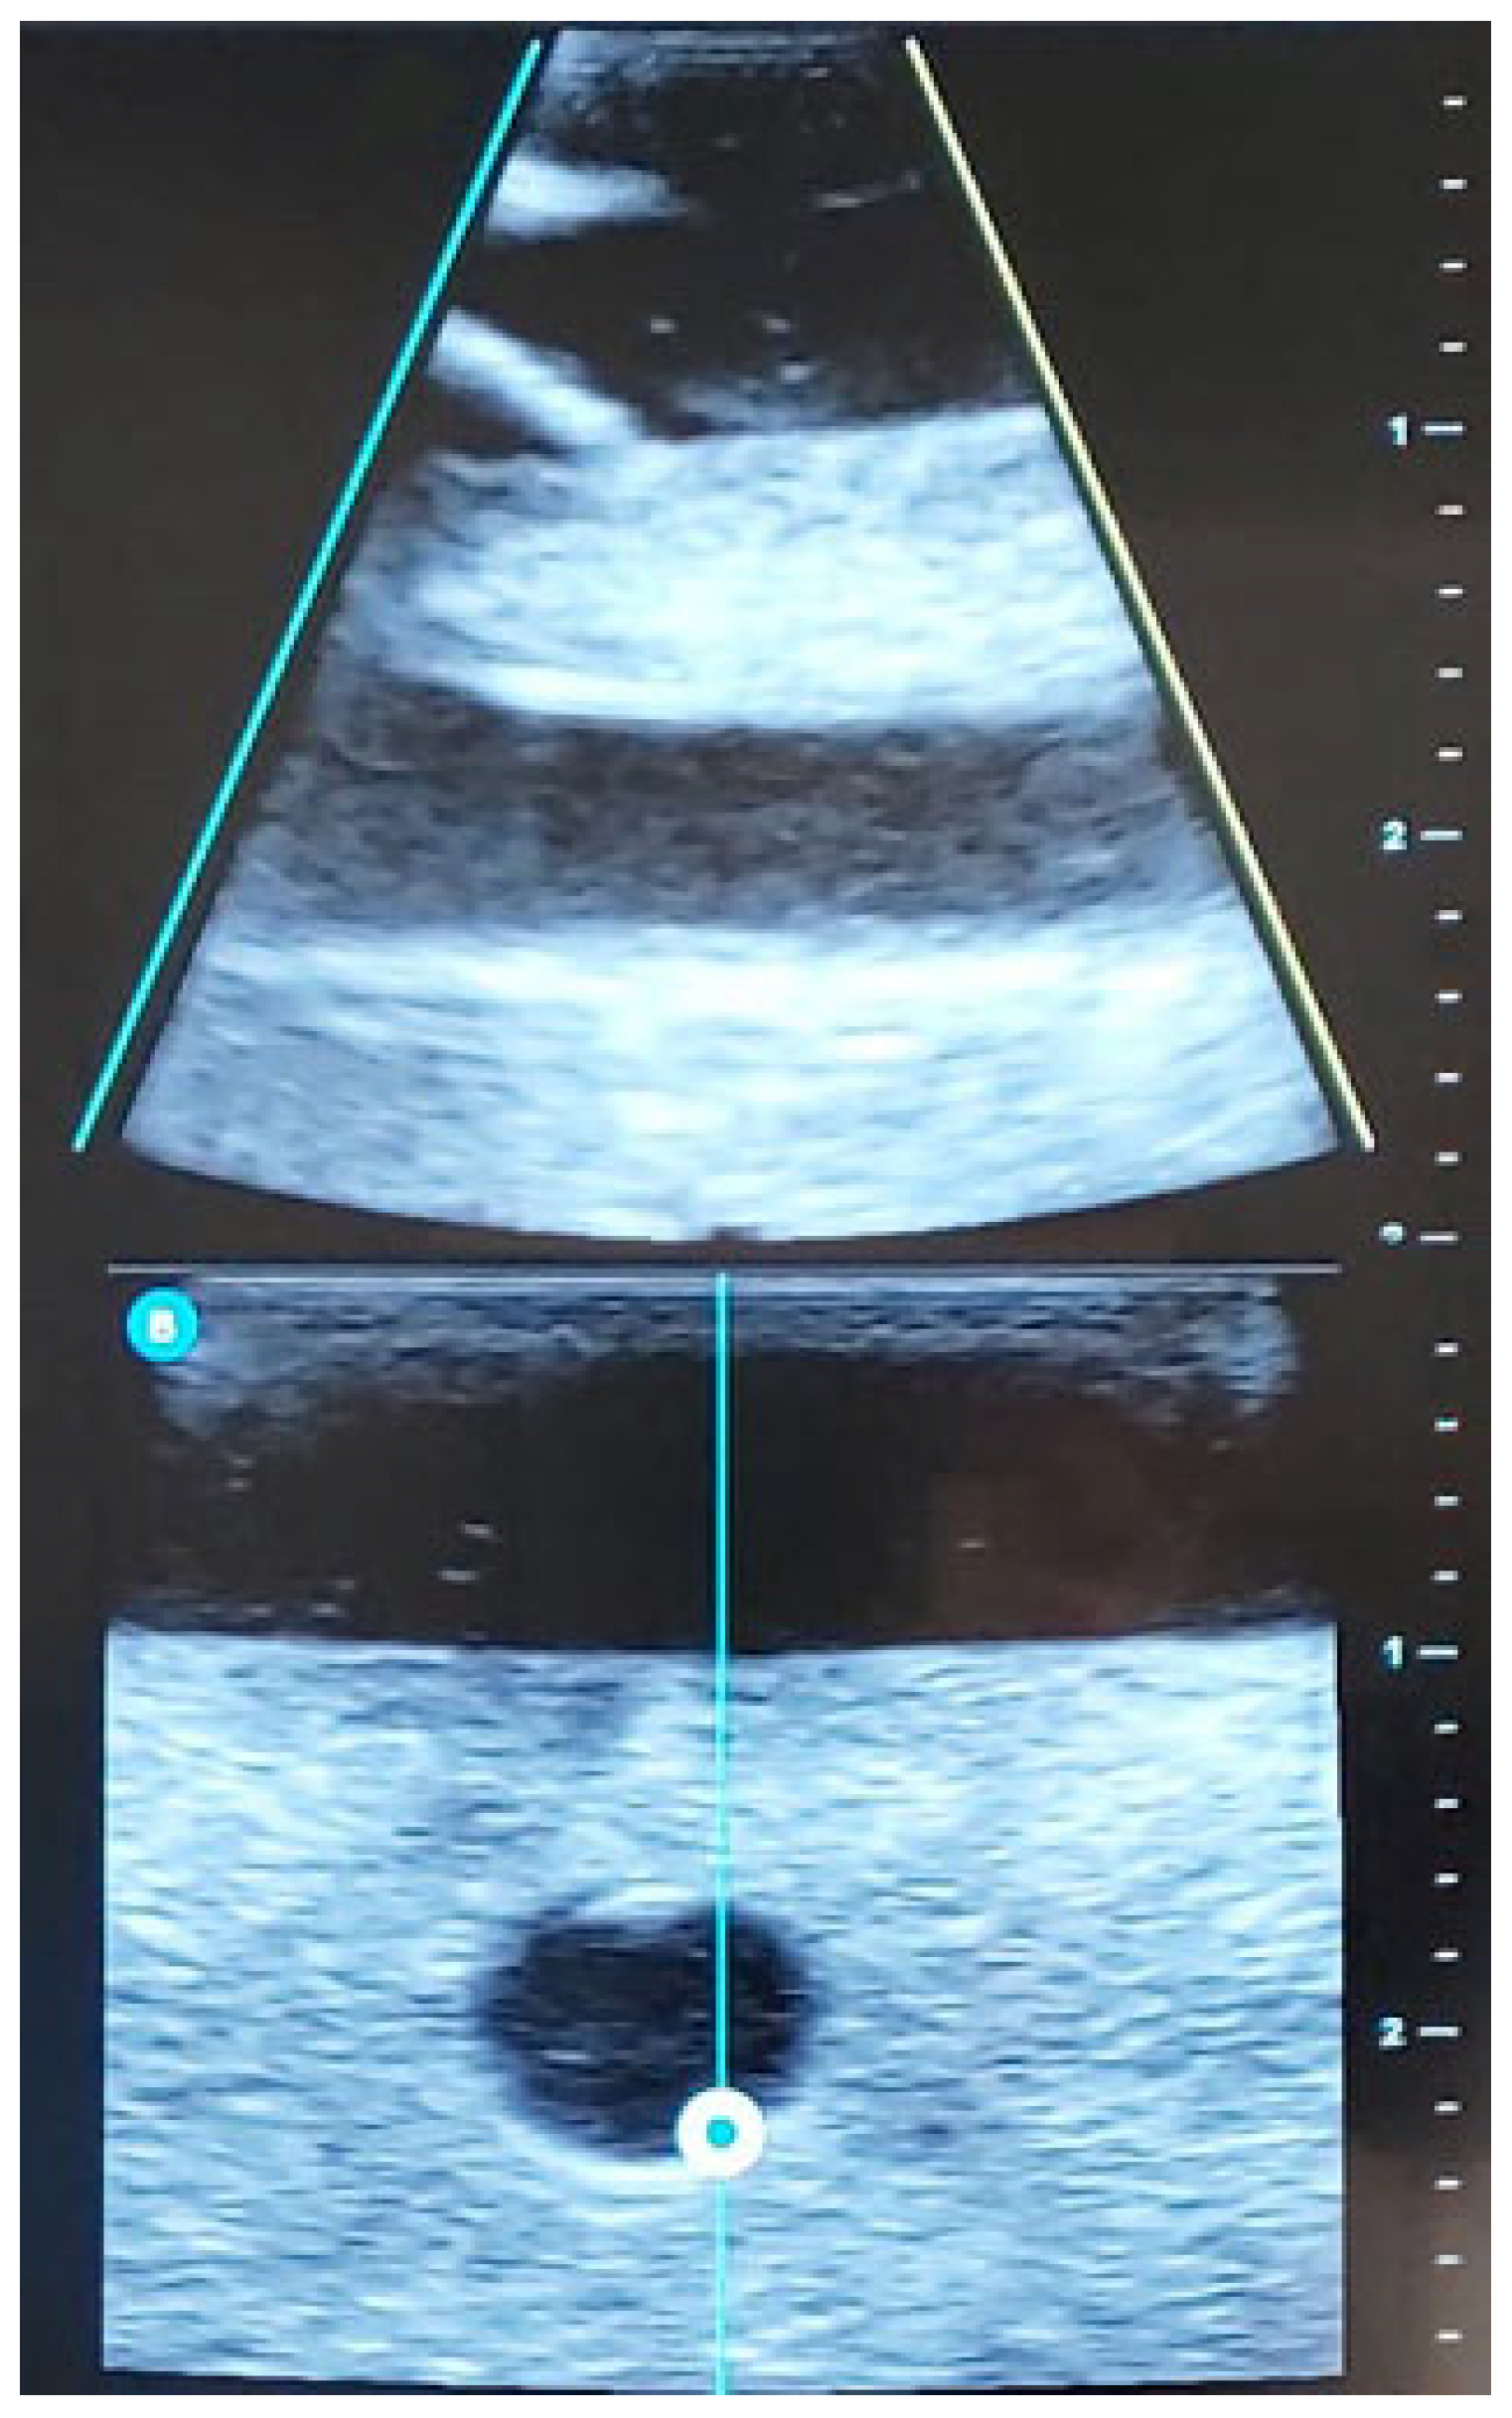

| STEP 3 | Ultrasound-guided examination of the limb to be punctured (RaPeVa):

| STEP 4 | Selection of an appropriate vessel (depth, diameter, and patency):

| STEP 6 | Ultrasound-guided puncture:

| Transducer placement | Longitudinal, transversal, none |